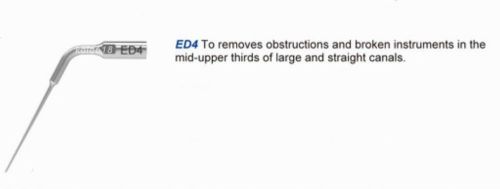

5* WP Ultrasonic Scaler Endodontics Tip ED4 DTE Satelec Handpiece Original kola

5PCS WP Ultrasonic Scaler Endodontics Tip ED3 Fit DTE Handpiece Original kola